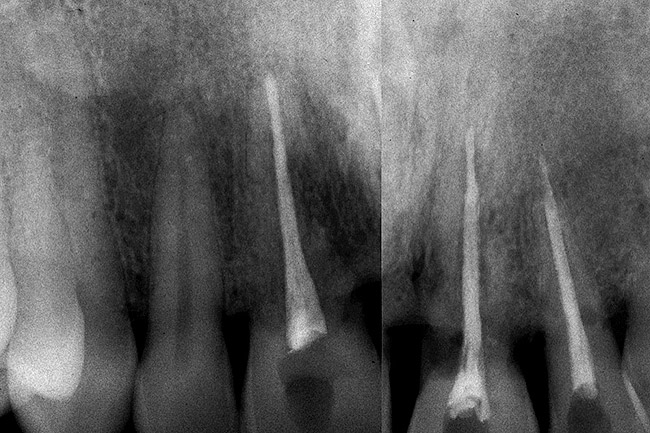

Figure 20  Soft-tissue levels were acceptable, but significant bone loss was present.

Figure 20

Figure 21  Eruption was used to attempt to move the bone coronally.

Figure 21

Figure 22  Following the eruption, there was minimal—if any—improvement.

Figure 22

Figure 23  The implants were placed.

Figure 23

Figure 24  Minimal gingival scallop because of the apically placed papilla and a long contact is the expected outcome in a patient with significant interproximal bone loss before implant placement.

Figure 24